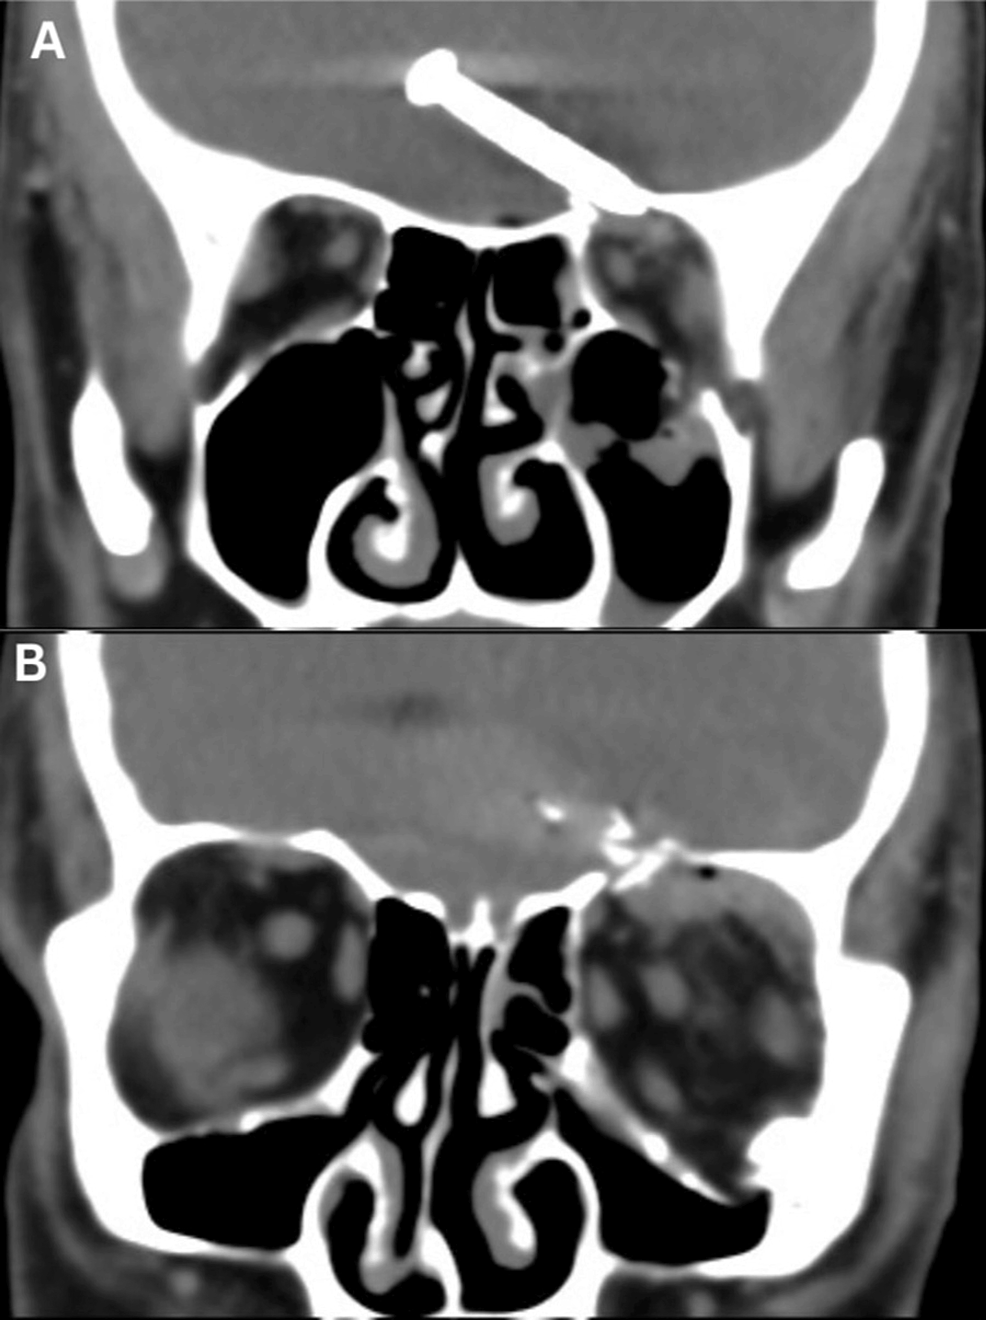

Bajo ese contexto, la herramienta dejó de funcionar y el hombre, cuya identidad no ha sido revelada, dio vuelta la pistola para ver cuál era el problema, pero se disparó accidentalmente y el clavo se enterró en su ojo.

Si bien el individuo estaba sin lentes de seguridad, el elemento no alcanzó a dañar el globo ocular, ya que entró por un costado del ojo. No obstante, llegó hasta el lóbulo frontal de su cerebro.

El hombre fue trasladado hasta el hospital Sultanah Bahiyah en Alor Setar, en Malasia, donde presentó una hemorragia interna en su cerebro, motivo por el cual se sometió a una cirugía para remover el clavo, logrando sobrevivir a pesar de las lesiones.